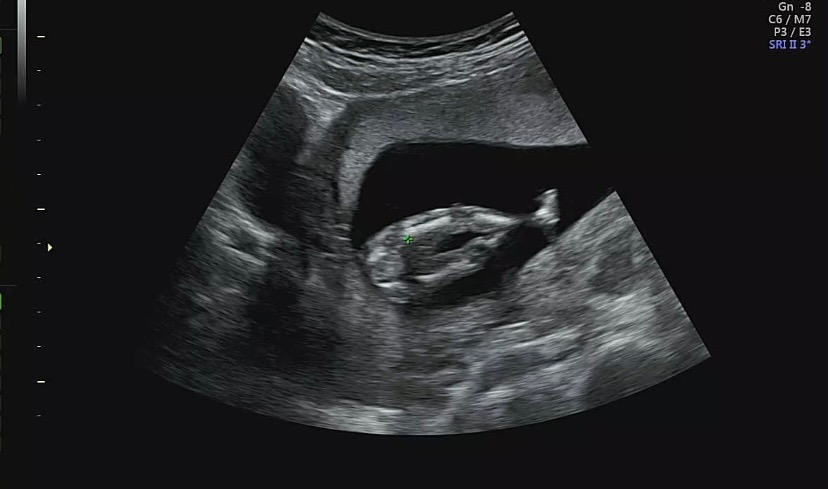

14주차 딸 맞을까요?

다리사이에 아무것도 없어보이긴 해서 딸이라 생각이 들긴 하는데 아들이면 다리꼬고 있으면 안보일수도 있나요?

딸같아보여요!아기가 롱다리인거같아용😀

딸이요~!

딸에1표여😊